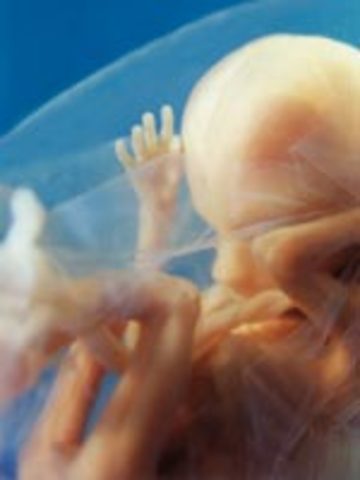

• Week 8

Week 8

The embryo now has little arms and legs in place, fingers and toes are visible. It is about 18mm and it begins to practice movement.